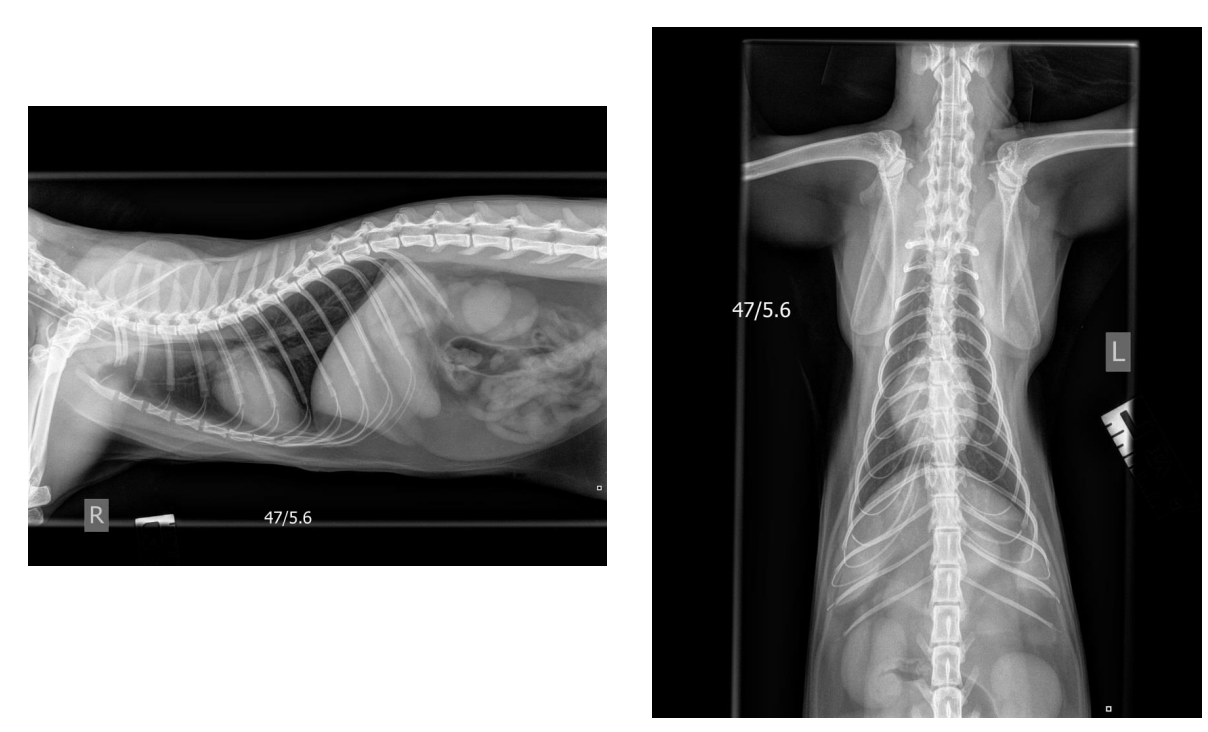

What anatomical features allow you to recognise this as a cat and not a dog?

Clavicle, square olecranon, long fine vertebral bodies etc

What is the triangular arrow pointing to and what does this tell you about the cat?

Endotracheal tube – cat was under GA

Why are all the abdominal structures so well delineated in this cat? Which organs can you recognise and what is labelled *?

Presence of intraluminal fat – radiolucent areas between organs.

Falciform fat

Liver, stomach, left and right kidneys, small and largeintestine